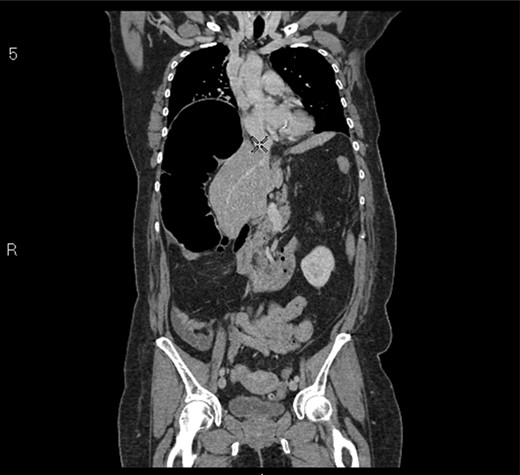

A 58-year-old female with a past medical history of a large intrathoracic hiatus hernia presented to her general practitioner and was subsequently referred to our surgical department with symptoms of sudden onset severe epigastric pain associated with vomiting and abdominal distension. Her abdomen was generally tender, maximally in the epigastric region, although she was not peritonitic. The admission erect chest radiograph showed a large hiatus hernia and an elevated right hemidiaphragm with a large loop of distended bowel (Fig. 1). Subsequent computed tomography (CT) scan demonstrated an almost completely intrathoracic stomach with a degree of volvulus, and the liver medially displaced by a loop of large bowel felt to be caecum (Fig. 2). Since the patient remained otherwise well, bidirectional endoscopy was performed, and given that a volvulus point could not be identified and the ileocaecal junction was not identified, contrast studies were requested (Figs 3–5) which demonstrated an incomplete obstruction caused by a volved caecum rotated anteriorly and cephalad.

CT coronal section demonstrating caecum medially displacing the liver and causing an upward pressure on the right hemidiaphragm.